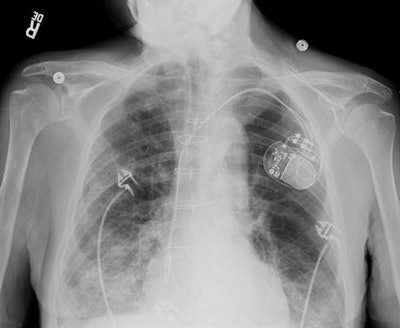

GE Healthcare developed its Discovery XR656 HD radiography system to reduce repeat imaging examinations. The unit includes FlashPad HD digital detectors, which have four times more pixels per area than previous technology, producing highly defined x-ray images, according to the company.

The firm's Helix image processing software enables workflow to continue smoothly, while the AutoRAD Suite supports the stitching of x-ray images. GE's Auto Image Paste tool supports seamless long-bone and spine x-ray studies.

Adult chest with pacemaker imaged using the Helix advanced processing tool. Image courtesy of GE Healthcare.Konica Minolta is promoting its AeroDR X10 mobile radiography system, a manually driven unit that's designed to deliver high performance, even in tight spaces. Equipped with the AeroDR flat-panel digital detector, the device features a 19-inch touchscreen display and AeroNAV software.